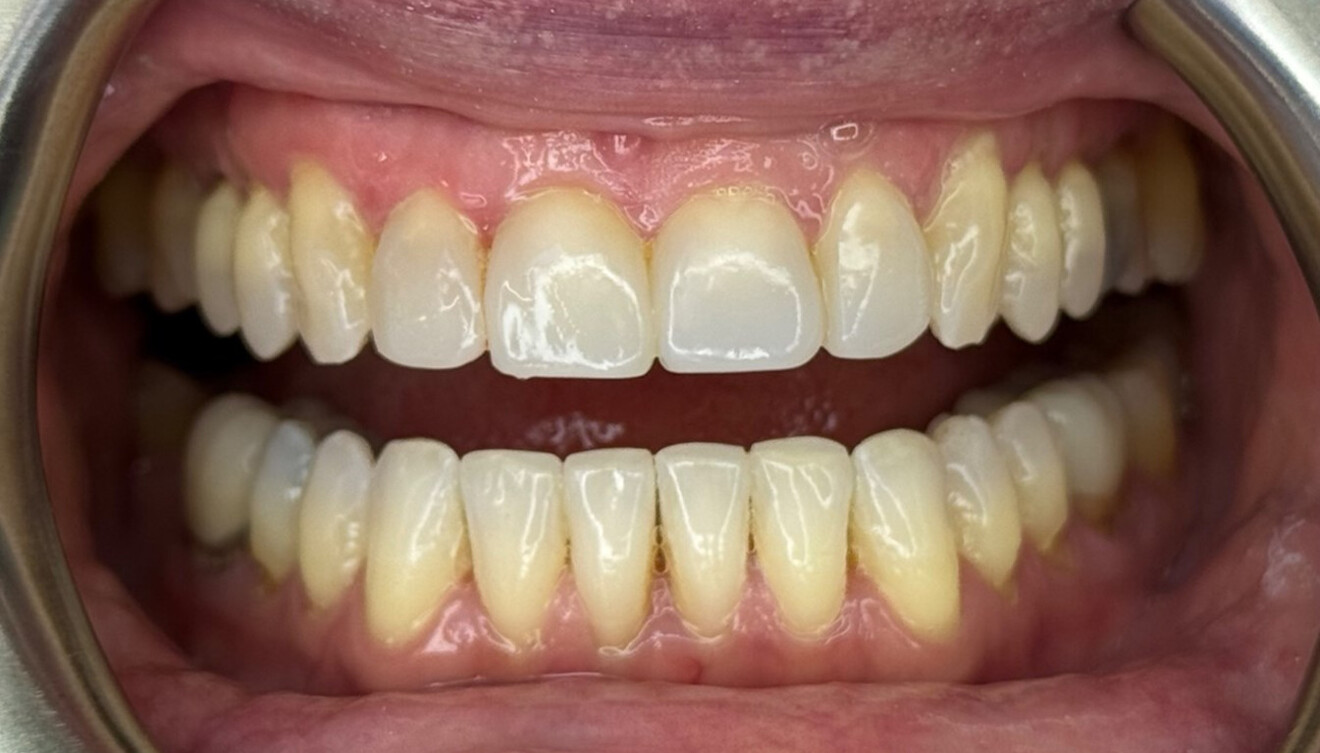

Fig. 4: Intra-oral pre-treatment photograph.